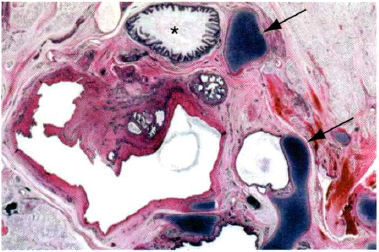

Q

What are the arrows seen in this image? And what is their classification?

A

Granulomas with necrotic centers and Caseating granulomas.